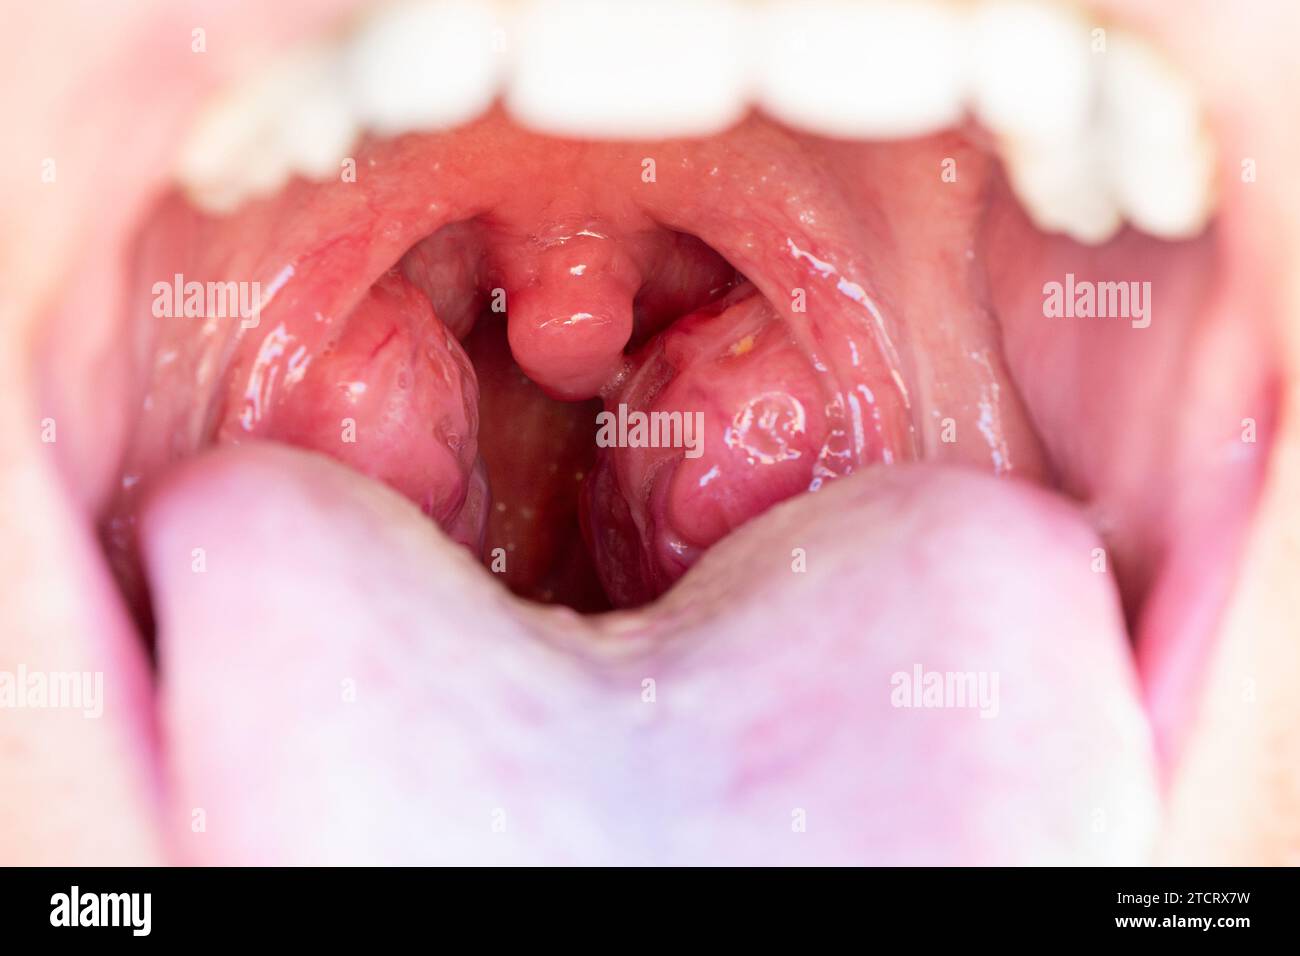

Nahaufnahme des offenen Mundes mit Mandeln. Das Kind ist ein Patient mit großen roten Drüsen. Tonsillen im Nahaufnahme im Mund. Stockfotohttps://www.alamy.de/image-license-details/?v=1https://www.alamy.de/nahaufnahme-des-offenen-mundes-mit-mandeln-das-kind-ist-ein-patient-mit-grossen-roten-drusen-tonsillen-im-nahaufnahme-im-mund-image575843517.html

Nahaufnahme des offenen Mundes mit Mandeln. Das Kind ist ein Patient mit großen roten Drüsen. Tonsillen im Nahaufnahme im Mund. Stockfotohttps://www.alamy.de/image-license-details/?v=1https://www.alamy.de/nahaufnahme-des-offenen-mundes-mit-mandeln-das-kind-ist-ein-patient-mit-grossen-roten-drusen-tonsillen-im-nahaufnahme-im-mund-image575843517.htmlRF2TCRX7W–Nahaufnahme des offenen Mundes mit Mandeln. Das Kind ist ein Patient mit großen roten Drüsen. Tonsillen im Nahaufnahme im Mund.